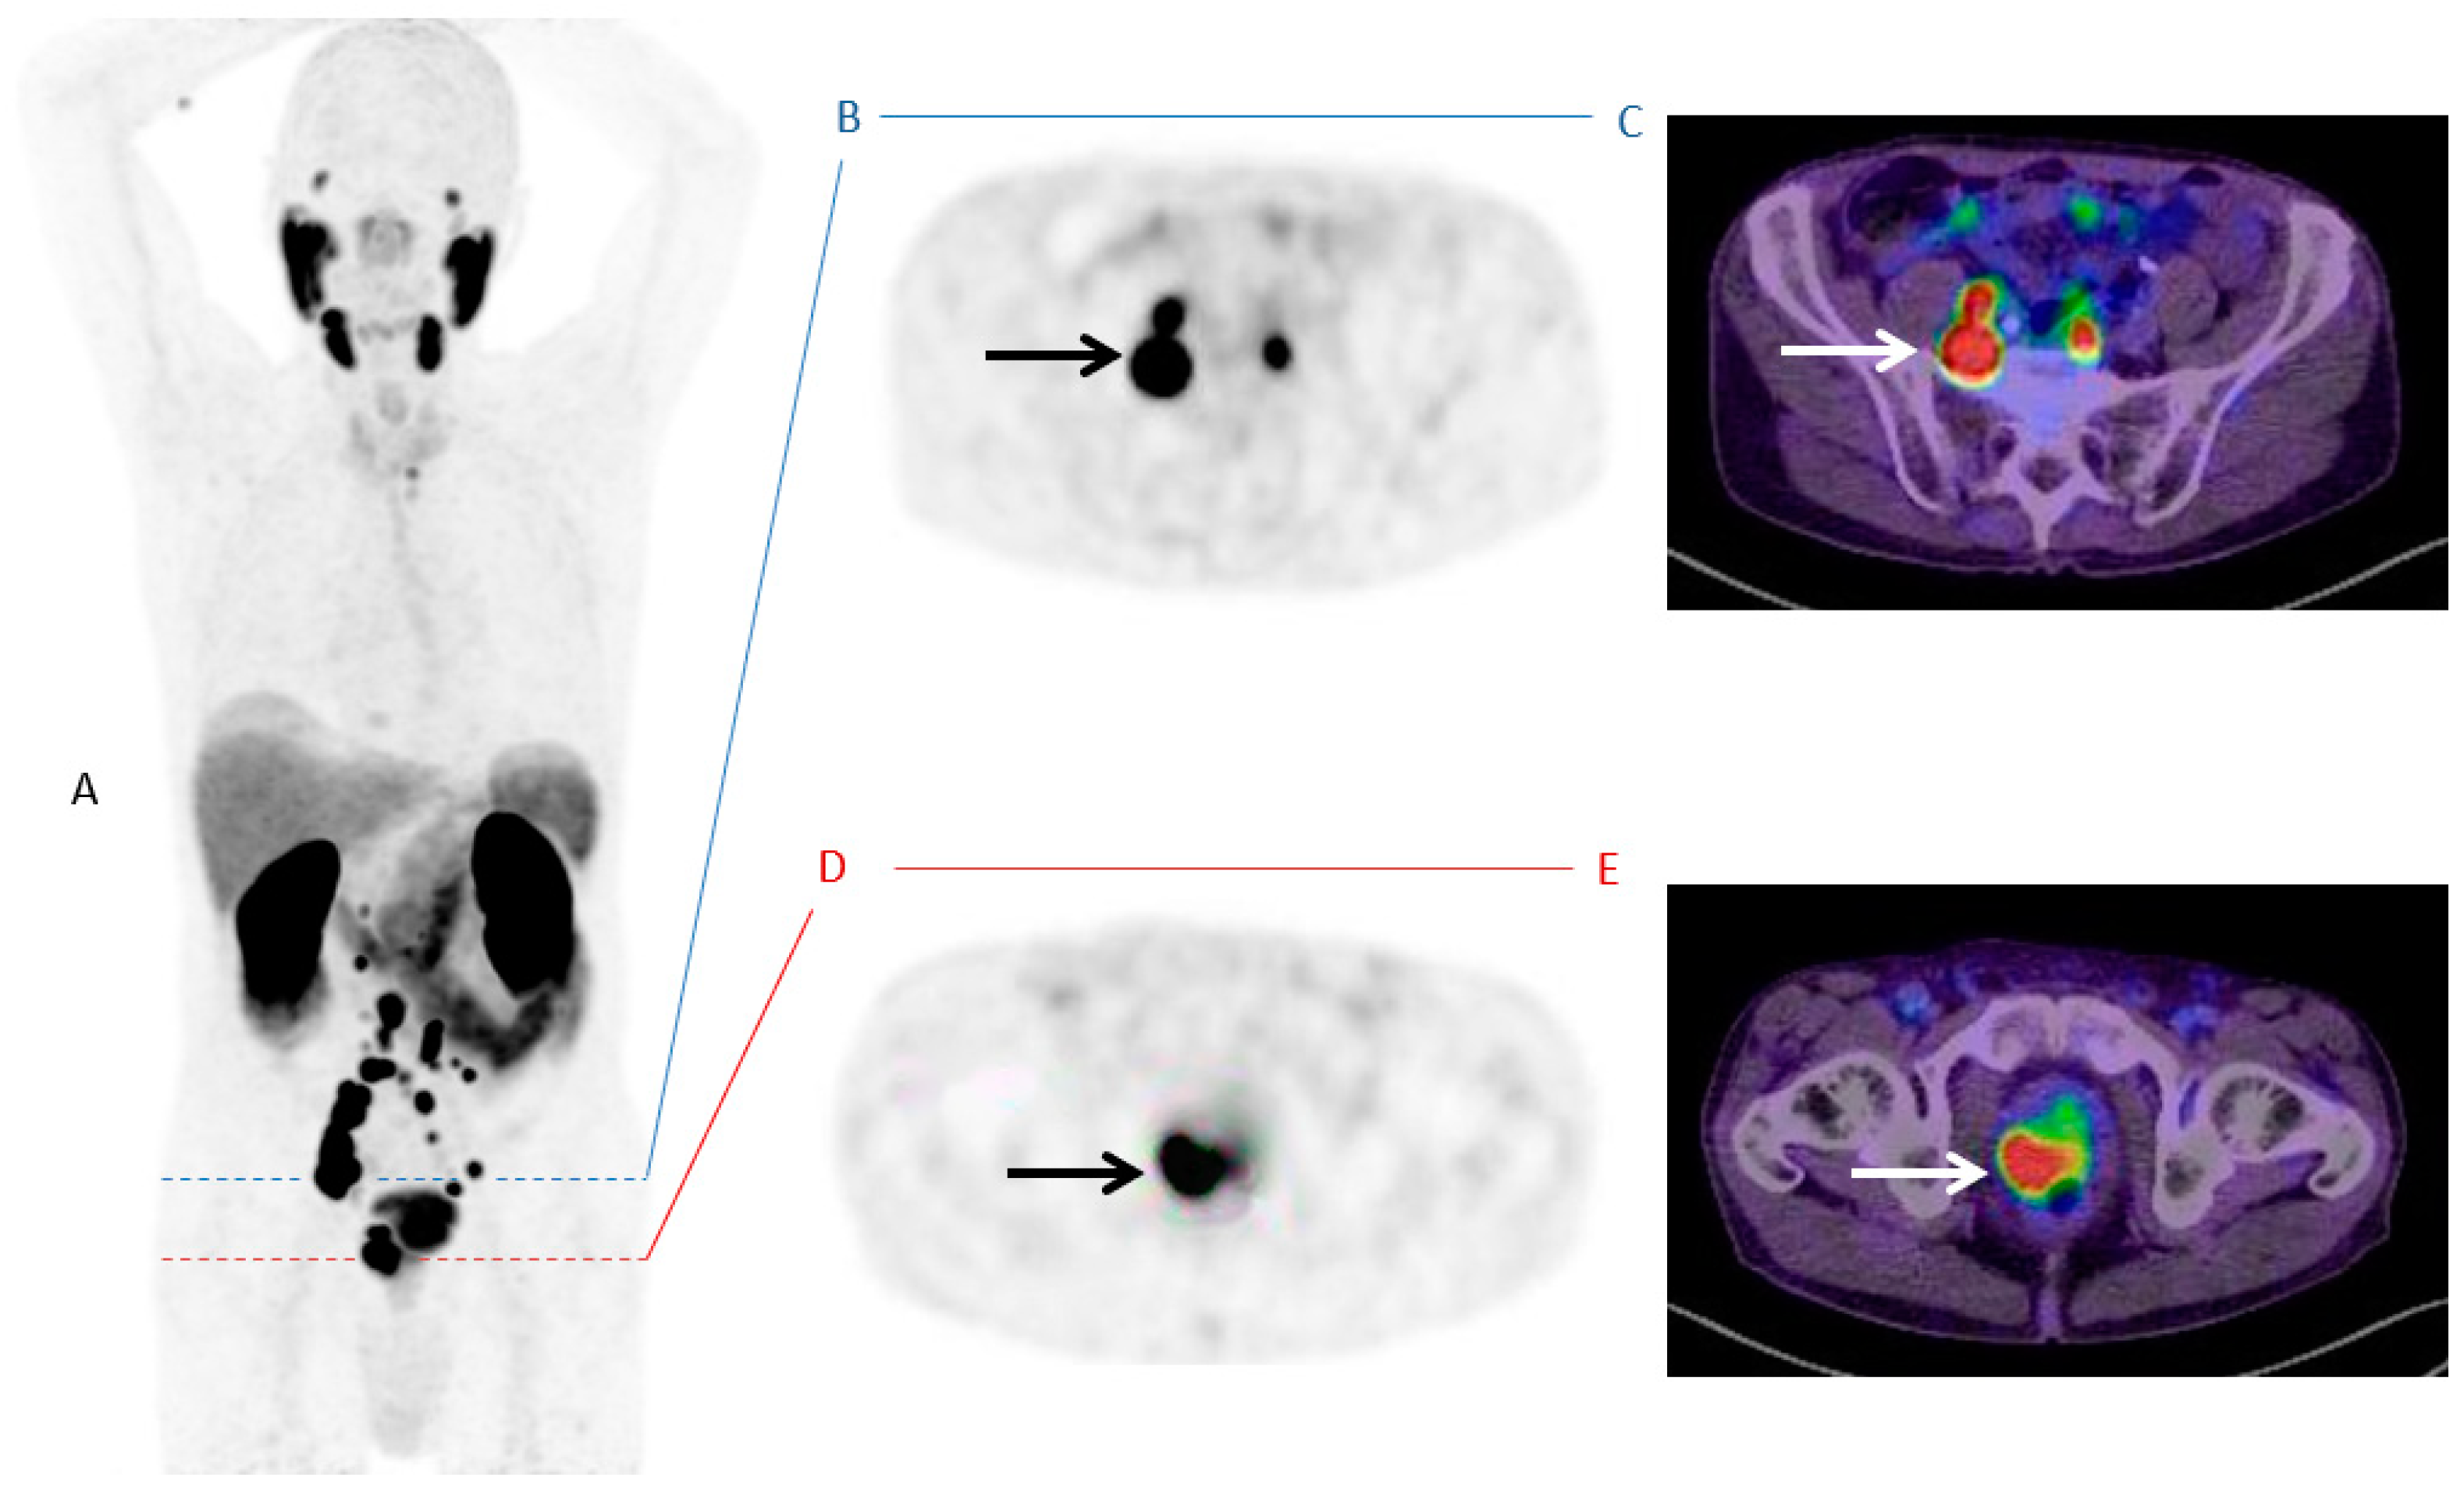

Until now, the identification of patient subgroups suitable for treatment escalation leading to improved survival is still challenging. Although numerous pretreatment risk stratification tools like the Memorial Sloan Kettering Cancer Center (MSKCC) nomogram or the Cancer of the Prostate Risk Assessment (CAPRA) score are available [27], there is a lack of evident data with regard to individual therapeutic consequences. Increasing numbers of PSMA-PET/CTs for primary staging around the globe confirms a great potential to that molecular imaging methodology. As published a few years ago, SUVmax of intraprostatic, malignant lesions was highly correlated with several clinical parameters like Gleason Score (GS) or PSA [28]. The present study observed a statistically significant higher SUVmax for men with metastatic disease (Figure 2 and Figure 3).

Figure 3.

PSMA-PET/CT in MIP (A) of a 83-years old patient with prostate cancer (GS 8/group grade 4; PSA 32 ng/mL) and high intraprostatic SUVmax (49.63) and several metastases; Level of prostate (B) PSMA-PET Dx; (C) PSMA PET/CT Dx; Level of nodal metastases (D) PSMA-PET Dx; (E) PSMA PET/CT Dx.